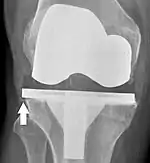

![]() |

Angles commonly measured before knee replacement surgery: |

To indicate knee replacement in case of osteoarthritis, its radiographic classification and severity of symptoms both should be substantial. Such radiography should consist of weightbearing X-rays of both knees: AP, lateral, and 30 degrees of flexion. AP and lateral views may not show joint space narrowing, but the 30-degree flexion view is most sensitive for narrowing. Full-length projections also are used in order to adjust the prosthesis to provide a neutral angle for the distal lower extremity. Two angles used for this purpose are:

- Hip-knee-shaft angle (HKS),[10] an angle formed between a line through the longitudinal axis of the femoral shaft and its mechanical axis, which is a line from the center of the femoral head to the intercondylar notch of the distal femur.[12]

- Hip-knee-ankle angle (HKA),[11] which is an angle between the femoral mechanical axis and the center of the ankle joint.[12] It is normally between 1.0° and 1.5° of varus in adults.[13]